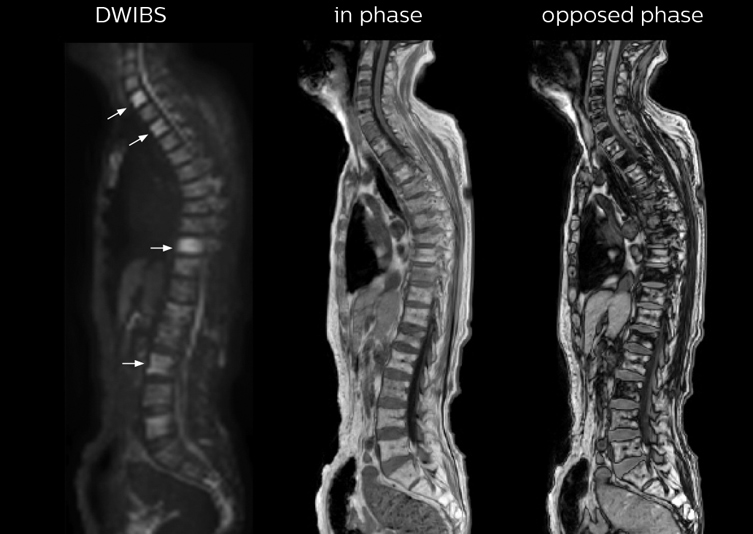

“In-phase and out-phase sagittal T1-weighted FFE images help us to visualize and further characterize bone lesions such as metastasis and bone-marrow hyperplasia that have high signal on DWI. These images are also used throughout radiotherapy, to monitor changes in the fatty bone marrow.”

“mDIXON FFE allows us to quickly get information we need to assess the presence of fat. That gives us more information when we need to diagnose bone lesions, and when we are asked to judge fat-containing lesions such as hepatocellular or renal carcinoma,” Dr. Nobusawa says. “The mDIXON fat images can help us to differentiate fatty bone marrow from bone lesions. This is especially useful in elderly people, who tend to have fattier bone marrow. The water images provide a high signal-to-noise ratio in the intestinal canal, which is valuable for visualizing lesions in the colon,” he says.

After implementing the improved whole body protocol, the radiology team initially did not see a large increase in referrals, although Dr. Nobusawa saw clinical cases where the DWIBS images provided him valuable information for diagnosis. This is why Dr. Nobusawa and Mr. Naka started to actively educate referring physicians about the value of whole body DWIBS. They organized several presentations for physicians in the hospital, where they explained how DWIBS can be of value in oncology patients. The information it provides can be useful for physicians when staging cancer, as well as when determining or adjusting treatment strategy. Mr. Naka remembers some cases where DWIBS provided remarkable information. “In one example, DWIBS visualized bone lesions that could not be seen on PET or SPECT. In another case we had found a bone lesion when a normal L-spine scan for narrowing of the disk space was done. One extra DWIBS scan (2 stations, 8 minutes) demonstrated a lesion that later was confirmed to be the primary region of cancer.”